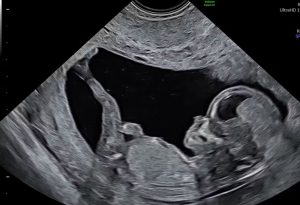

In Nederland kennen we een drietal abortusmethoden:

– Tweede trimester abortus (D&E vanaf 12 weken), zie video voor uitleg

De curettage behandeling is gelijk aan de curettagebehandeling na een miskraam. Hiervoor worden dezelfde instrumenten gebruikt en dezelfde methodiek. Het enige verschil in de twee situaties is dat bij abortus het kindje nog leeft voor de behandeling en bij curettage na een miskraam het kindje al is overleden.